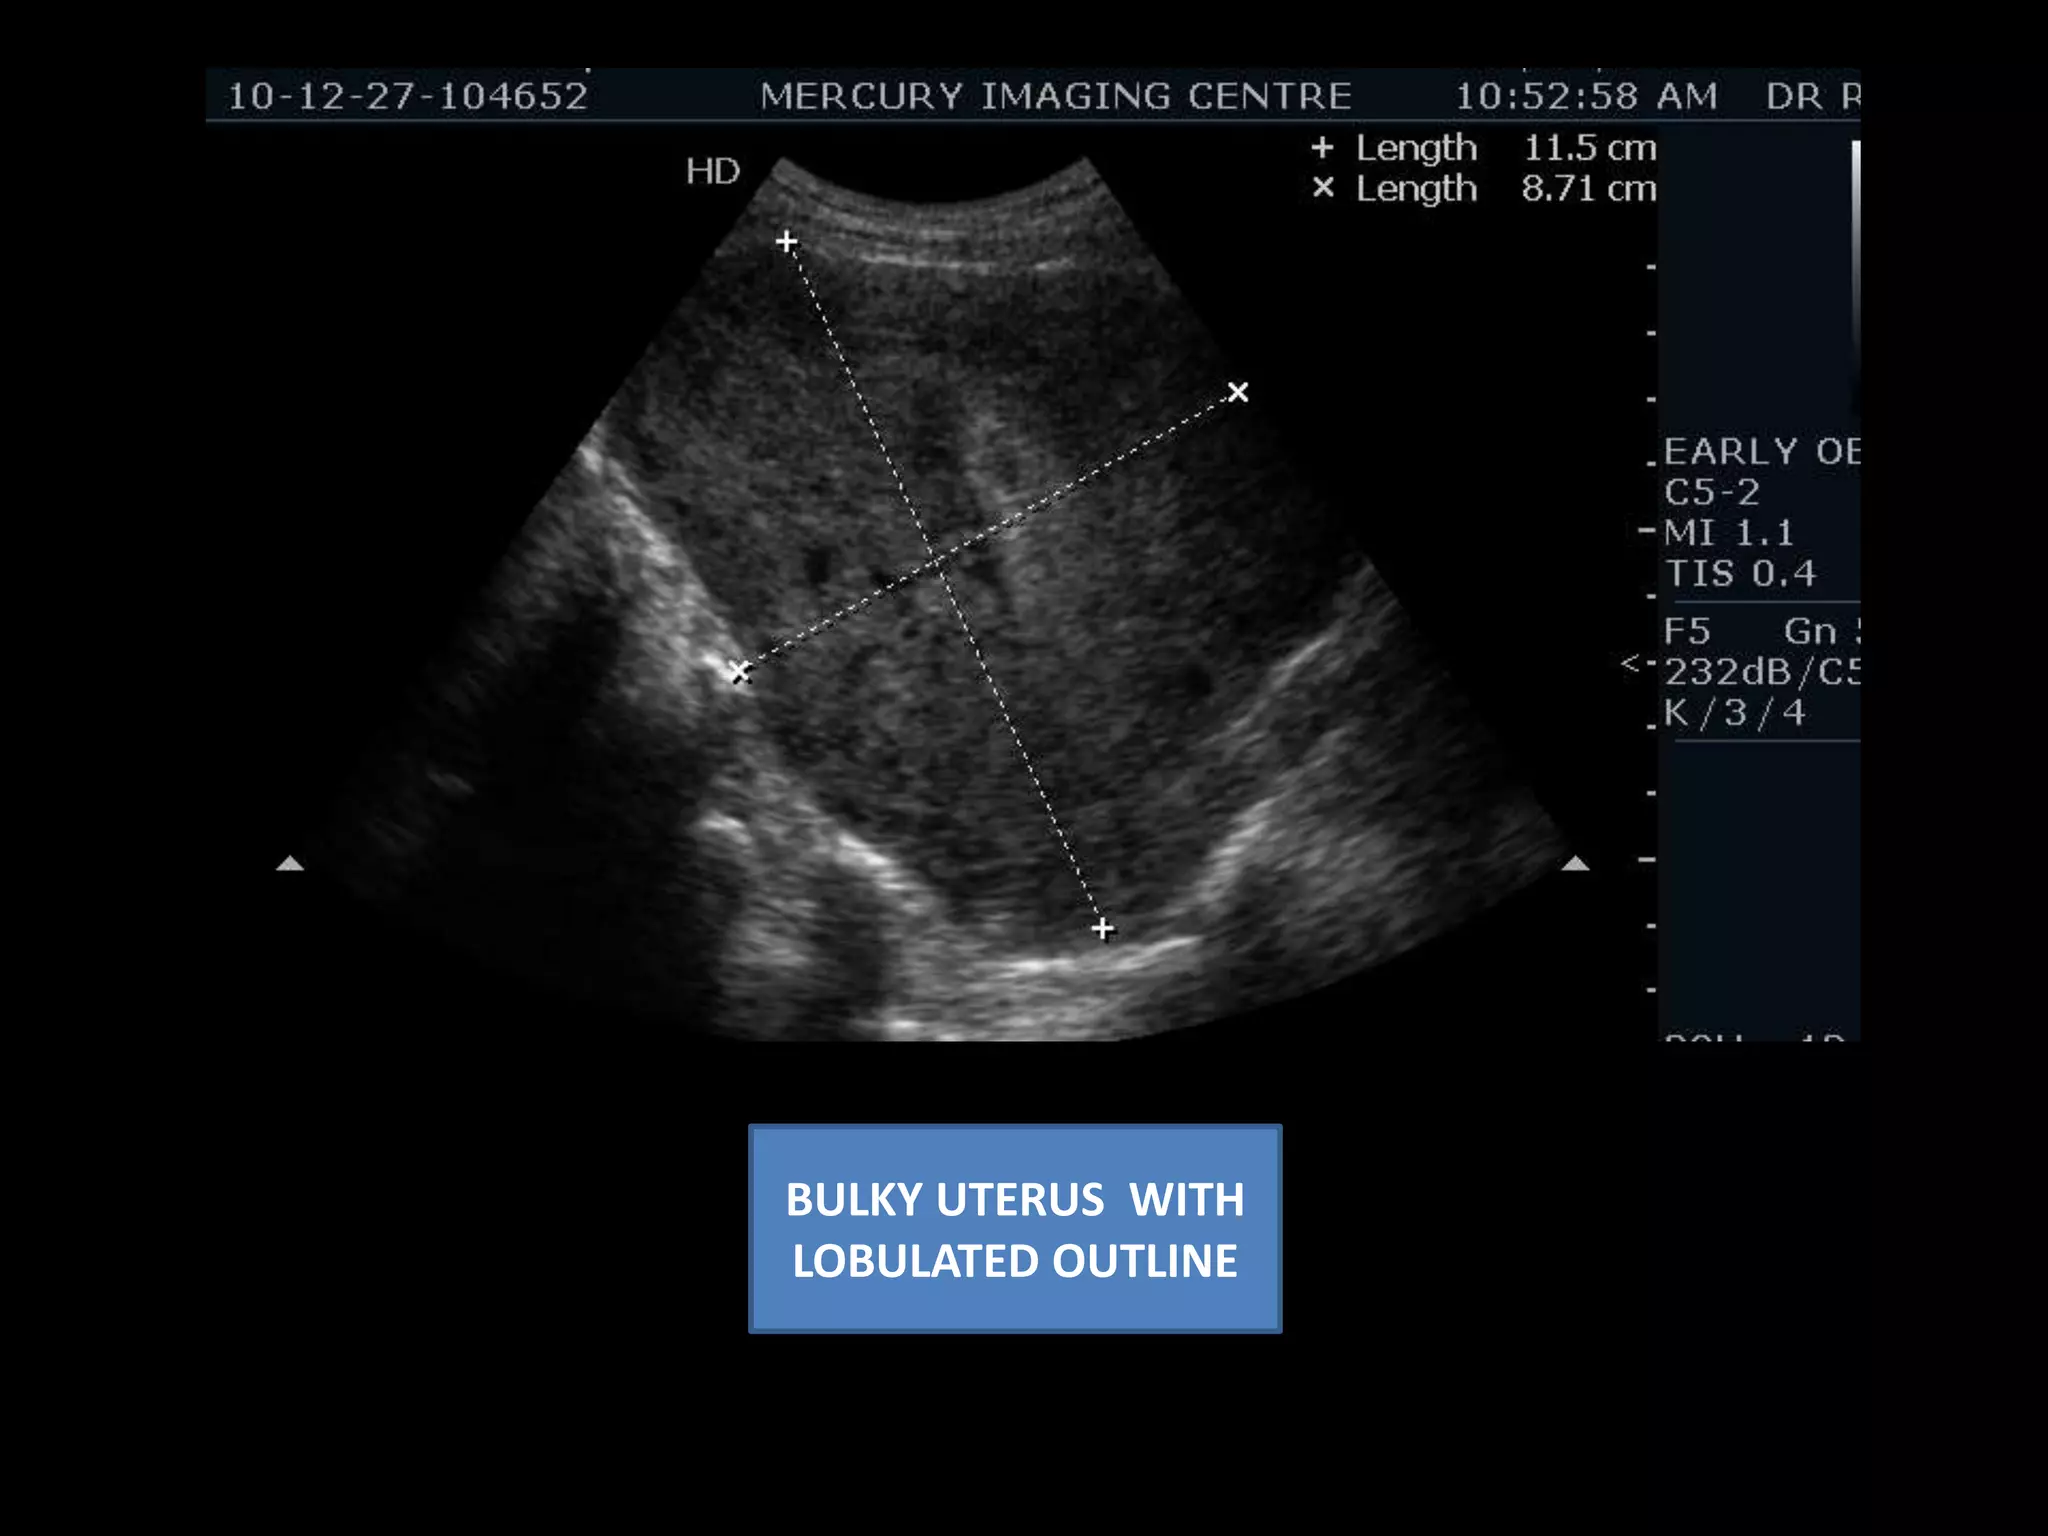

Present case ...................... Bulky uterus with lobulated outline

BULKY UTERUS  WITH LOBULATED OUTLINE

Present case ......................Bulky uterus with lobulated outline